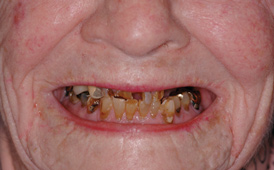

The Toronto Conference in 1982, chaired by Professor George Zarb and presented by Professor Per-Ingvar Brånemark, was a seminal event that changed edentulous treatment planning concepts irrevocably. No longer was it necessary to rebuild lost bone through grafting alone in either arch. The severely atrophic mandible, for example, could be treated with as few as four implants used to support a bone-sparing prosthesis through integrated tooth analogs, as demonstrated in Figure 1 through Figure 3. Here, an 81-year-old patient presented with severe mandibular atrophy (Figure 1) from denture wear since a very young age and had a history of being unable to manage a mandibular prosthesis despite numerous attempts at new denture construction. Four vertical machined-surface osseointegrated implants were placed in 1983 by Professor Brånemark, and all four penetrated the inferior cortex up to 3 mm to 4 mm in depth, as shown on the immediate postoperative panoramic film (Figure 2). At 4 years and 5 months, reparative bone had formed to the apices of all implants (Figure 3), and all of them remained in uncompromised function until the patient passed away at age 90.

Fig 1. 81-year-old patient had severe mandibular atrophy from many years of denture wear and had a history of inability to manage a mandibular prosthesis.

Figure 1